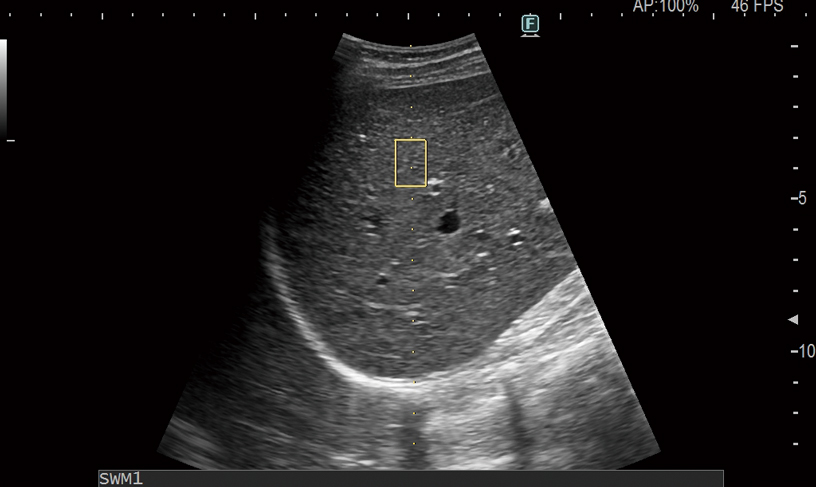

Evite procedimientos complejos como biopsia o MRI con nuestras características de ultrasonido de onda de elasticidad fáciles de usar. Las ondas de elasticidad se generan usando un “pulso de empuje” para excitar los tejidos. SWM proporciona una evaluación de la rigidez del tejido mediante el cálculo de Vs, la velocidad de propagación de las ondas de elasticidad. Gracias a nuestro índice de confiabilidad único, la rigidez hepática puede evaluarse con información cuantitativa y capacidad de reproducción altamente precisas. El SWE codifica por color la rigidez del tejido en función de la velocidad de propagación de las ondas de elasticidad. Ambos se pueden usar para evaluar el hígado de manera visual y no invasiva, y para permitirle determinar con precisión la estadificación de la fibrosis. Además, la medición de la ATT, para calificar el nivel de infiltración adiposa, utilizando el coeficiente de atenuación, se combina con la medición de la onda de elasticidad para un enfoque multiparamétrico completo para el manejo de la enfermedad hepática crónica.

Al integrar los dos métodos no invasivos para la evaluación de la rigidez del tejido hepático, a saber, RTE y SWM, es posible evaluar la progresión cronológica de la inflamación y fibrosis hepáticas con mayor precisión. Una estimación simultánea combinada del grado de esteatosis (índice ATT) hace de Combi-Elasto una herramienta integral para el diagnóstico diferencial de la enfermedad hepática.